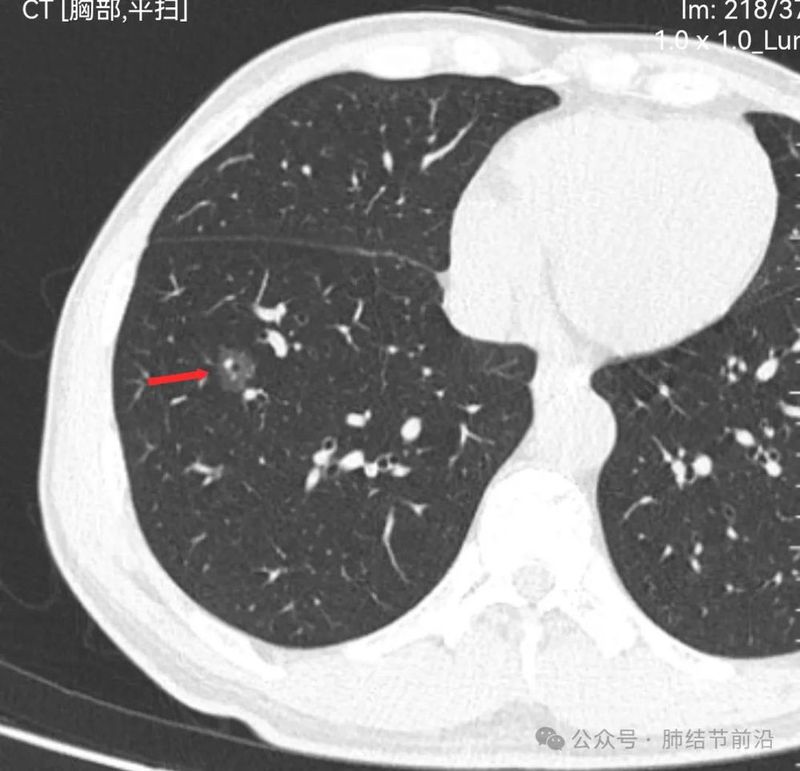

61岁女性,无吸烟史,2024年7月行冠脉CT时发现右肺下叶磨玻璃结节14mm。后续马上复查肺部薄层CT。

见右下肺纯磨玻璃结节14mm。有“血管穿过”、空泡。磨玻璃边界清楚而不毛糙。形态上是典型的肿瘤性磨玻璃,以微浸润腺癌可能大。